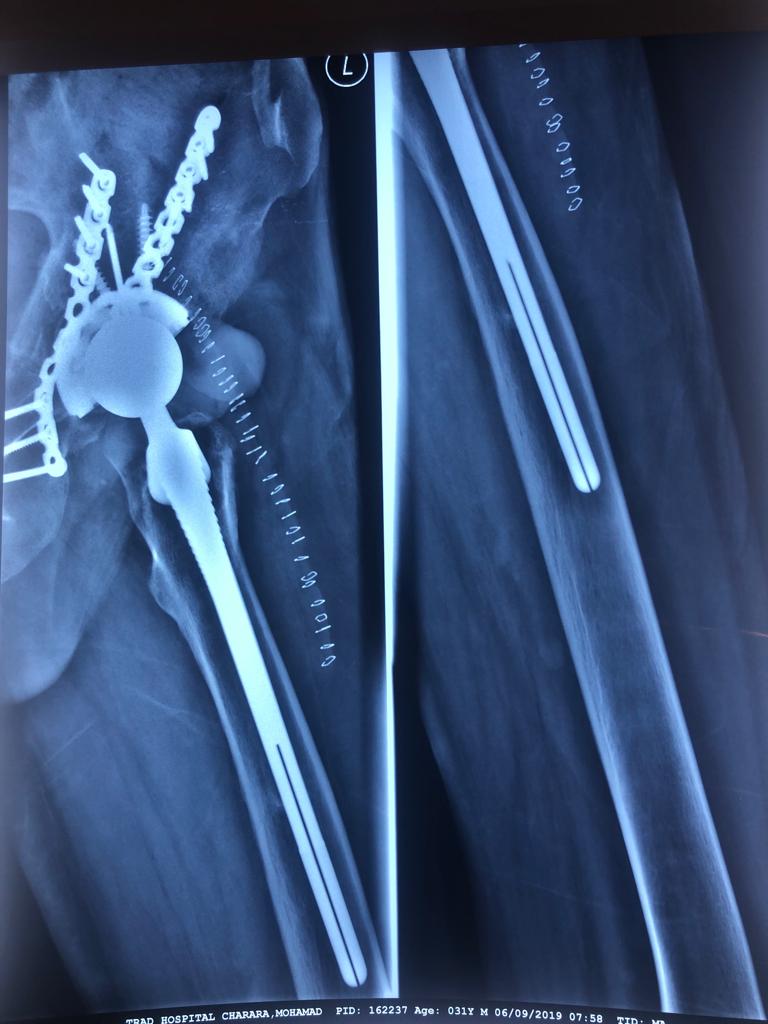

Revision Total Hip Arthroplasty Femoral Stem